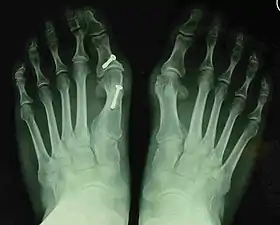

Fig. 8a. Painful hallux valgus and metatarsus primus varus deformity recurrence of left foot after osteotomy surgery